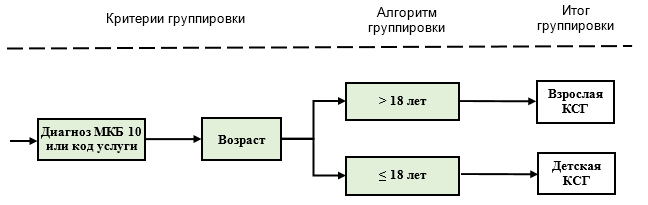

Категории возраста применяются в трех аспектах, не предполагающих одновременное (совместное) использование всех категорий возраста для классификации случаев в одни и те же КСГ.

3-й аспект применения: диапазоны возраста 5-6 используются для классификации случаев в большое количество "детских" и "взрослых" групп. При этом, если случай хирургического вмешательства ребенку до одного года может быть классифицирован в КСГ st10.001 или КСГ st10.002 (приоритет), он классифицируется в эти группы. Во всех остальных случаях классификация осуществляется в соответствующие КСГ с применением кодов возраста 5-6.